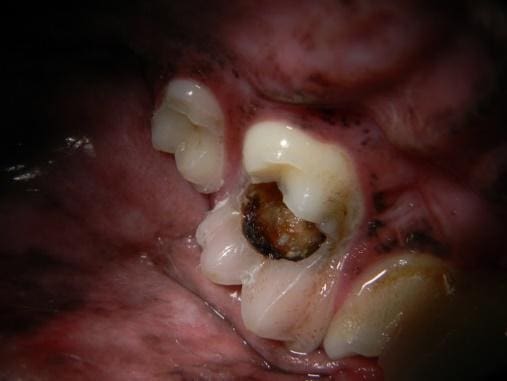

Figure 5. (A) A molar a cavity that can be treated with a restorative filling and (B) a tooth with an end-stage cavity that requires extraction.

(A)

(B)